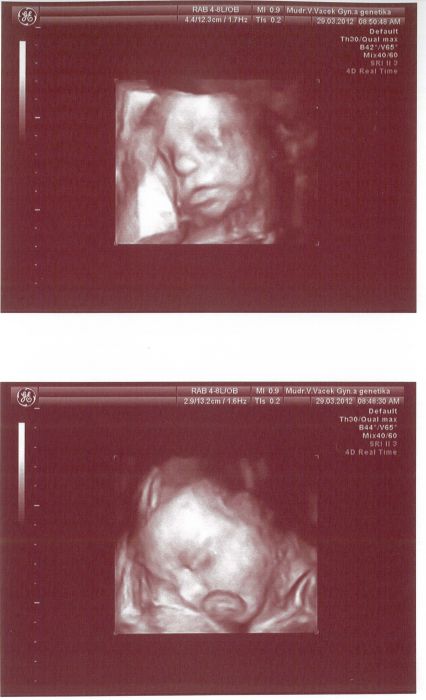

Kočky, nejde tam toho moc vidět, na druhý fotce má před pusinečkou pupečník.....( je nenapapanej po mamince) ale alespon něco jde v isět, jako na třetí pokus.....

Nikoušku moc hezký

mě se líbí právě ta druhá...to je úplně jak kdyby spinkal v postýlce a v pusince dudlíček